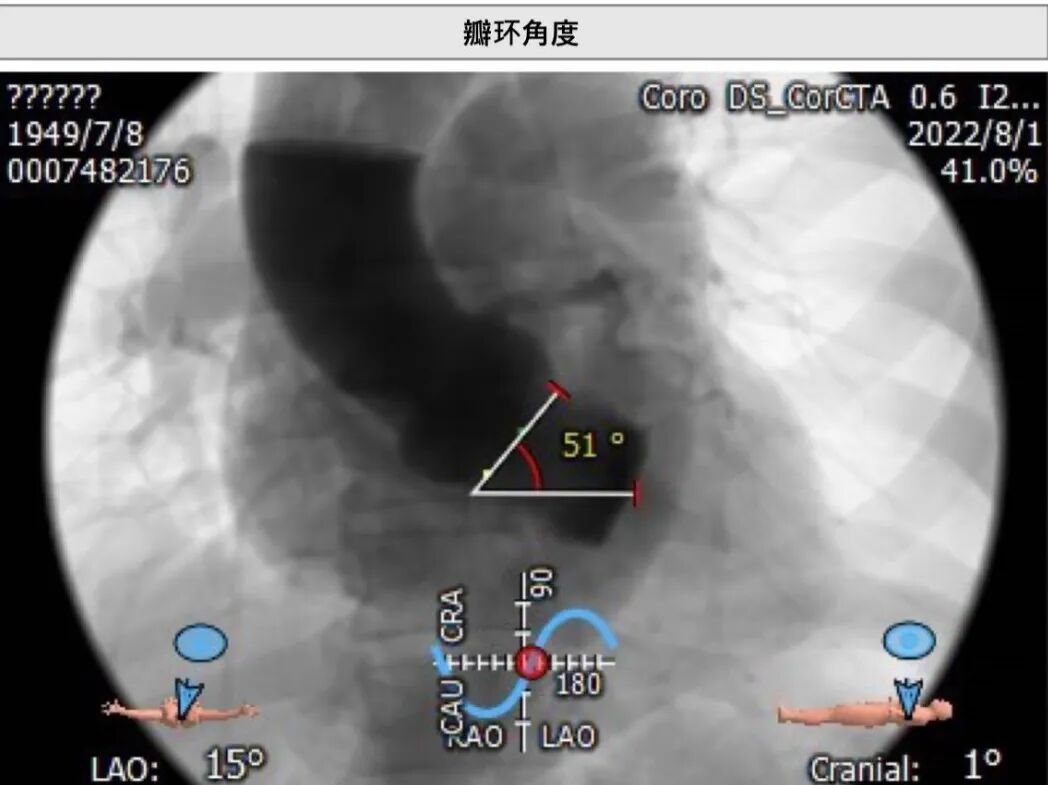

主动脉根部CT测量

瓣环周长:77.5mm

LVOT周长:74.4mm

左冠高:16.8mm瓣叶长:15.7mm

右冠高:16.1mm瓣叶长:16.2mm

瓣环角度:51o

升主周长:112.8mm